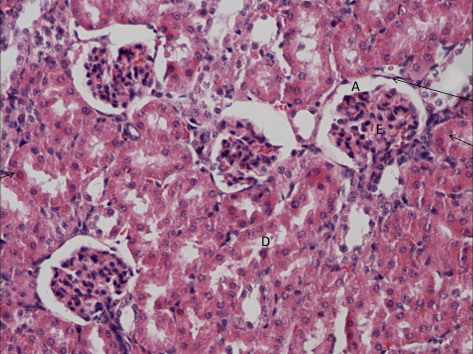

nabłonek jednowarstwowy płaski na zewnętrznej stronie blaszki torebki Bowmana

ścianki kanalika proksymalnego to nabłonek jednowarstwowy sześcienny

NERKA - kora nr 430

światło kanalika proksymalnego i kłębuszek nerwowy (ciałko Malpigiego)

brzeżek szczoteczkowy